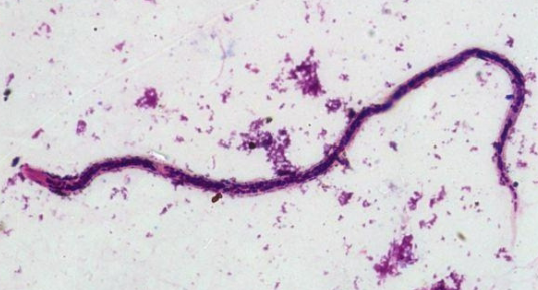

Trypanosoma spp.

Trypanosoma spp.